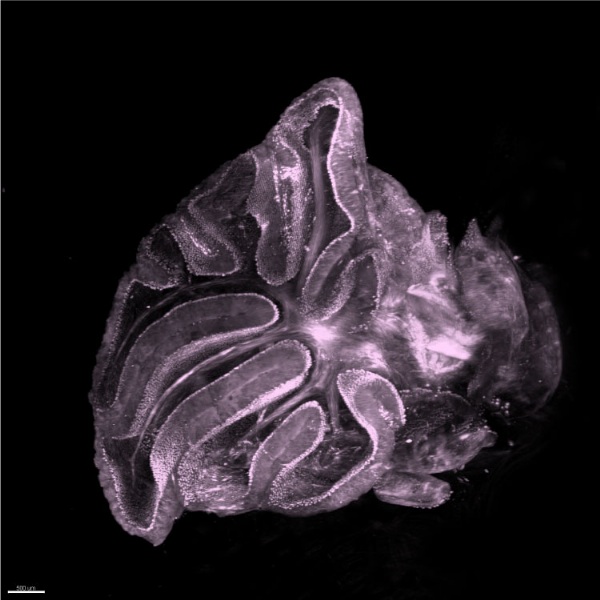

諾倫科技結合專利技術與自有研發團隊,創立3D病理影像技術平台,且為提供高品質、高穩定的3D病理影像,推出一站式的3D全組織病理影像服務。

目前可將厚達1.5cm的小鼠腦與各式鼠類器官進行3D影像掃瞄成像,也能執行2mm的腫瘤組織。

諾倫科技結合專利技術與自有研發團隊,創立3D病理影像技術平台,且為提供高品質、高穩定的3D病理影像,推出一站式的3D全組織病理影像服務。

目前可將厚達1.5cm的小鼠腦與各式鼠類器官進行3D影像掃瞄成像,也能執行2mm的腫瘤組織。